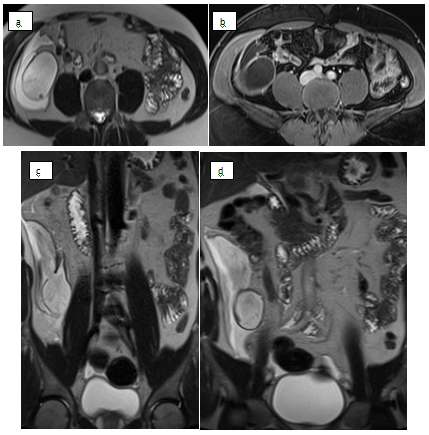

MRI reveal dialted tubular structure in right iliac fossa communicating with the cecum shows high signal with periphreal hypointense rim in T2 weighted images (a,b&c) keeping with known calcification seen by CT. Post-contrast axial image (b) shows periphral enhancement. Focal defect in wall (shown by arrow in c) which is continuous with surrounding fluid confirm rupture of mucocele (Figure 2).

Figure 2 MRI images.